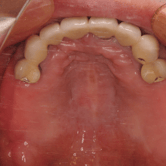

Edentulismo completo

El edentulismo completo es la ausencia total de dientes en una o ambas arcadas.

Los pacientes tienen dificultad para masticar, hablar y pueden sentirse incómodos con su apariencia.

El tratamiento puede incluir la colocación de una prótesis completa sobre implantes, proporcionando una solución fija y estable